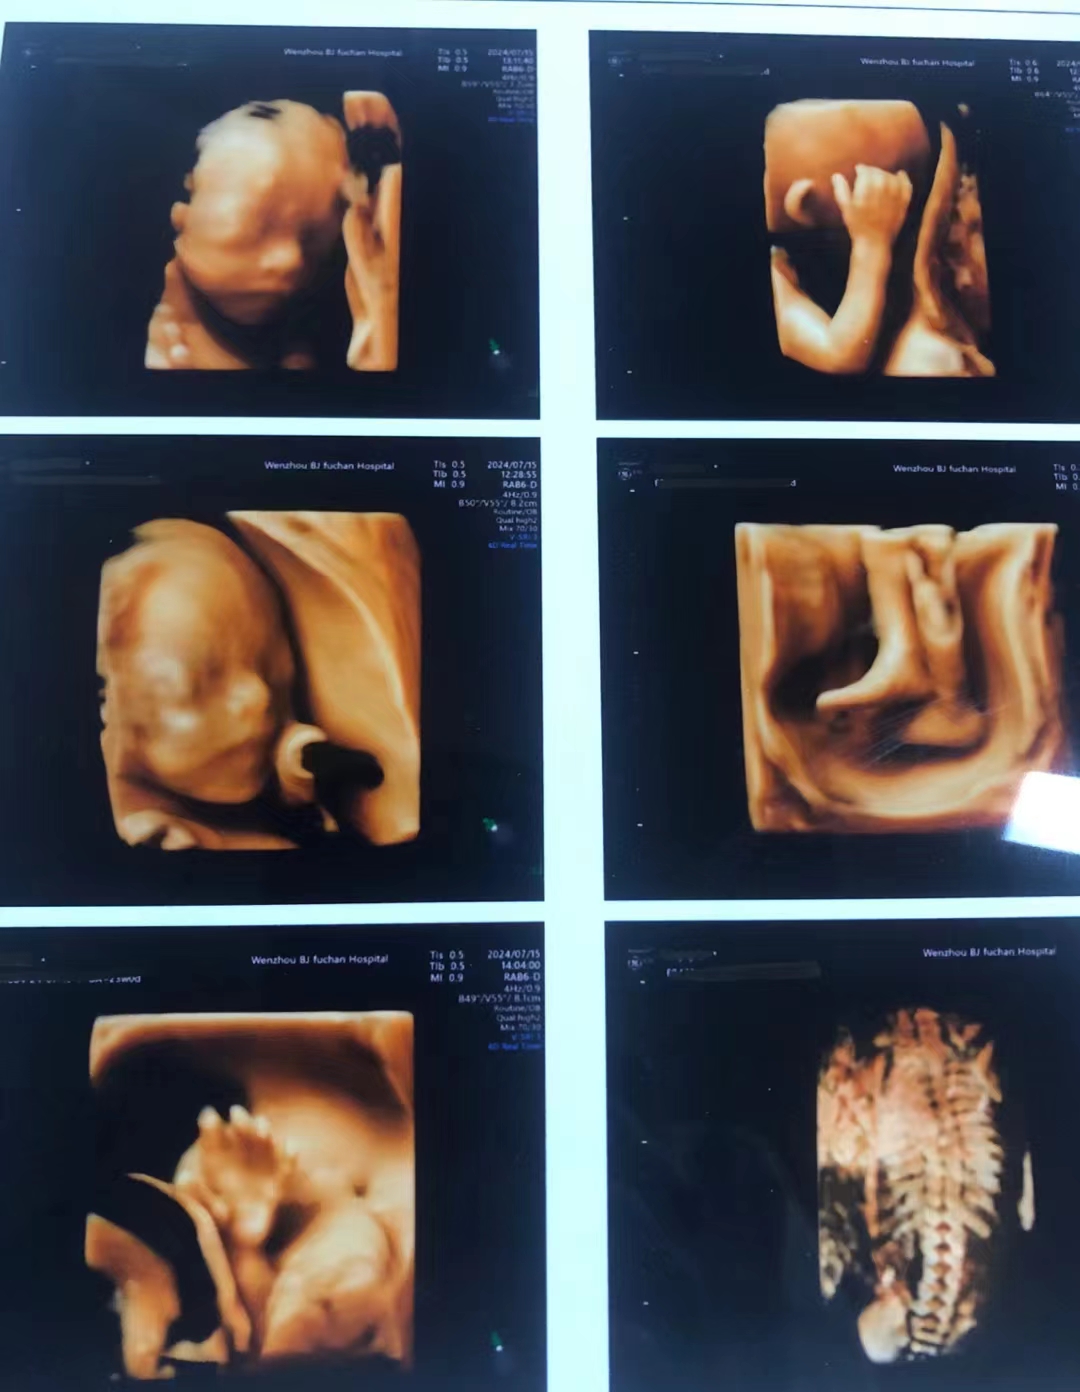

龙港孕妈必看!温州百佳东方四维彩超超全预约攻略!

医院:温州百佳东方妇产医院

地址:温州市鹿城区车站大道79号

亮点:专业的妇产专科医院,服务和环境都超nice!